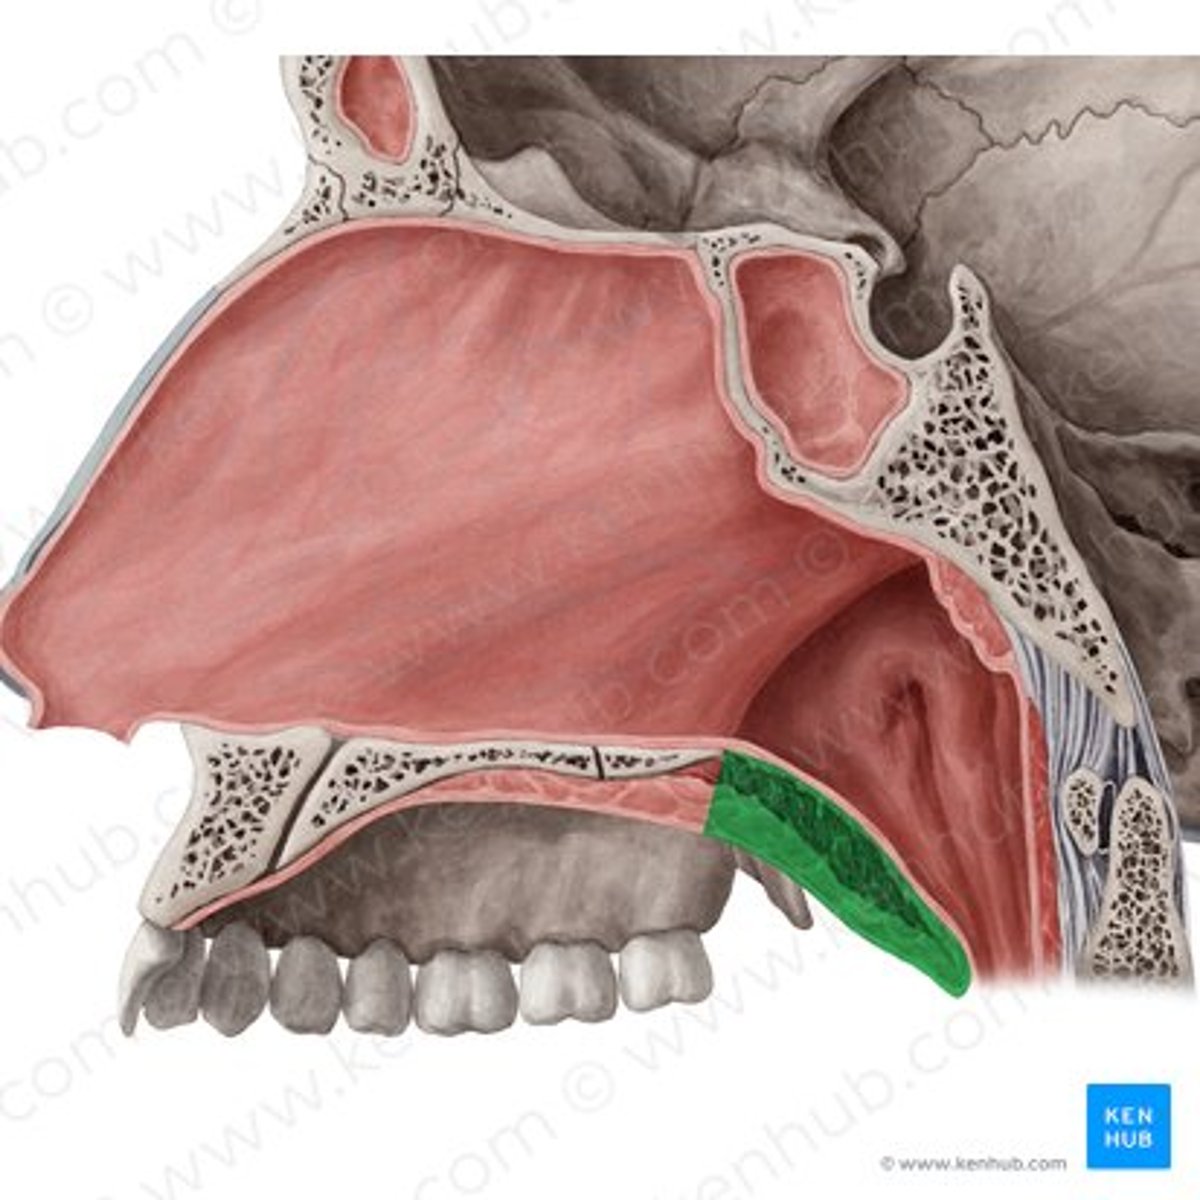

hard palate

palatine bone (horizontal plate)

maxilla (palatine process)